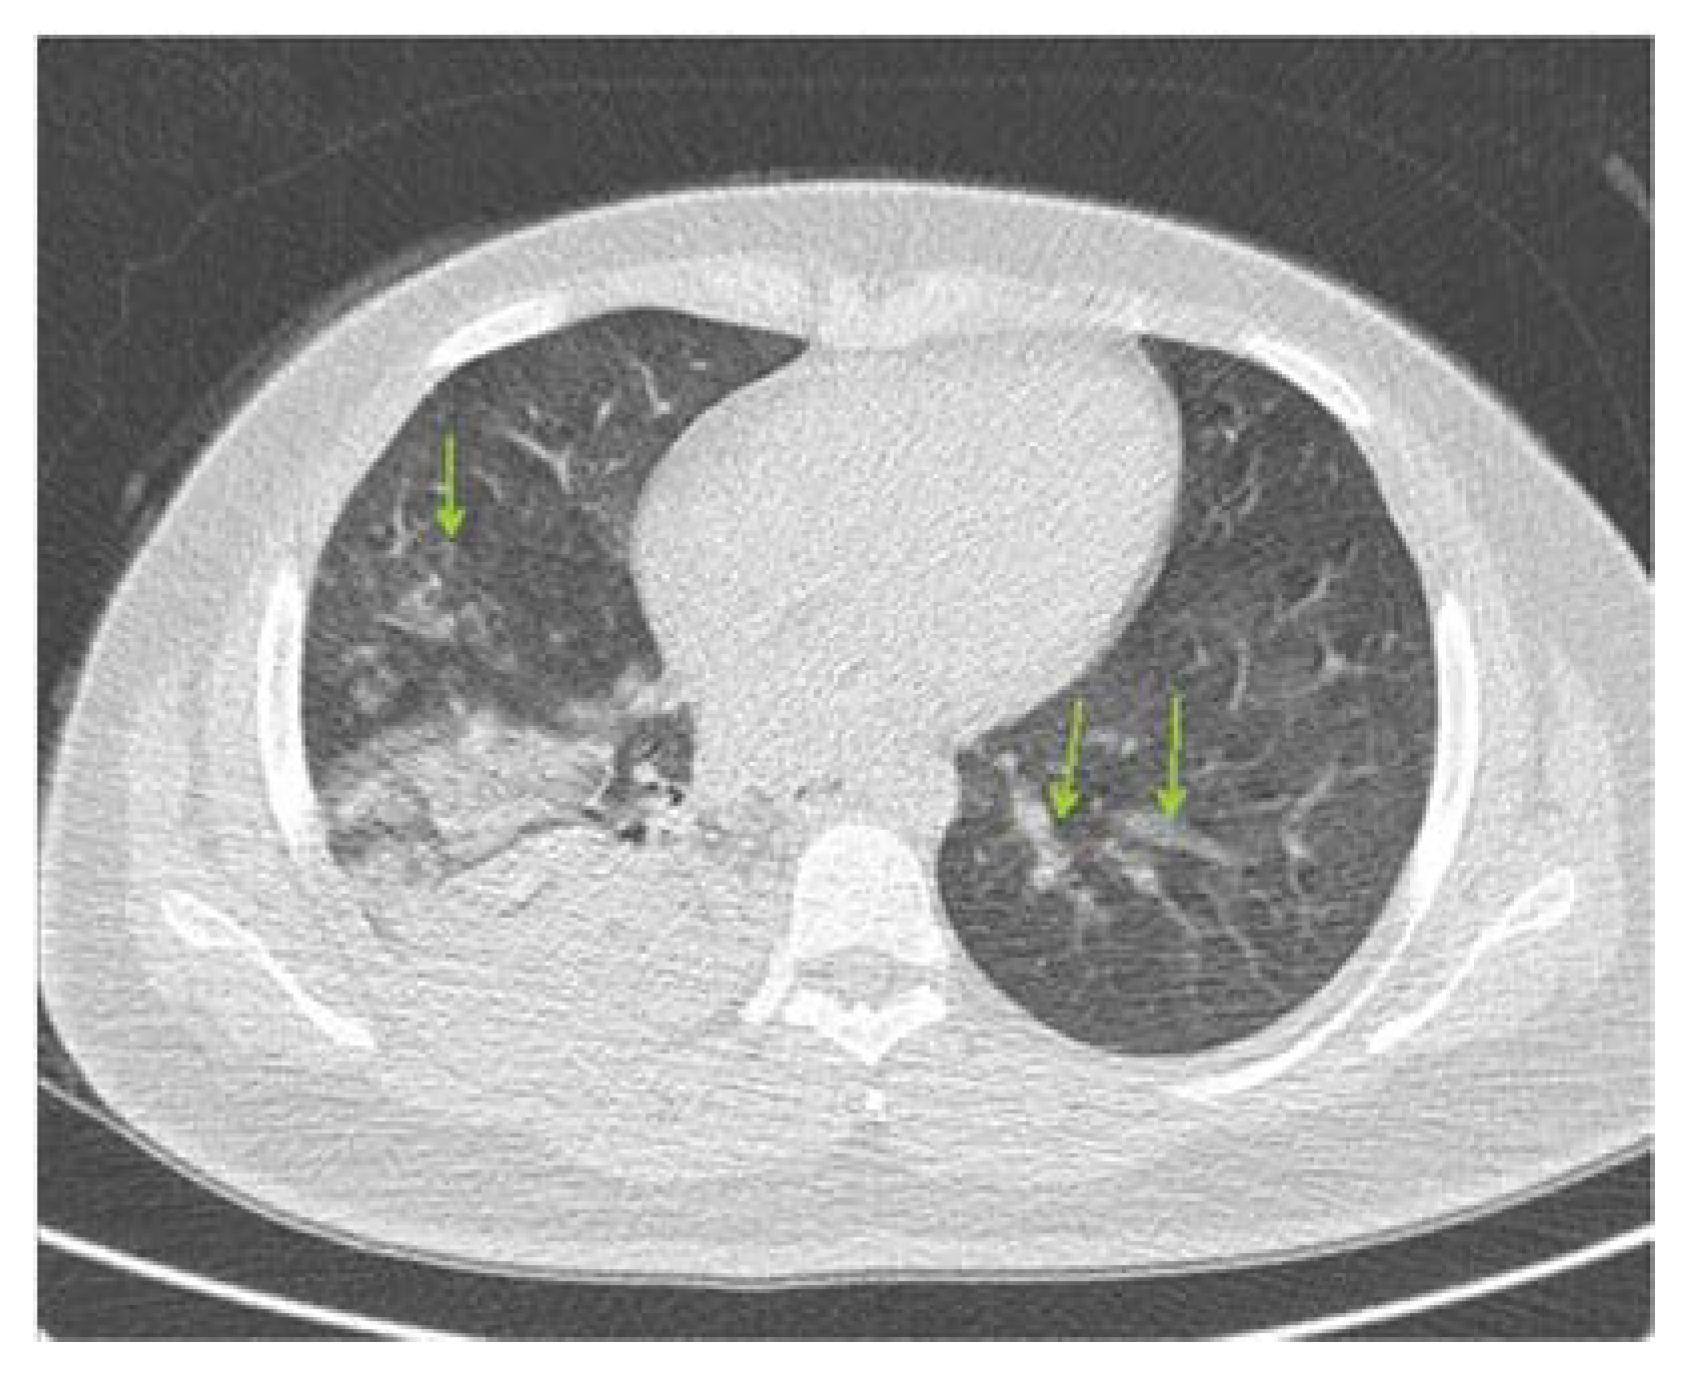

2.1. Patient Introduction and Initial Conditions